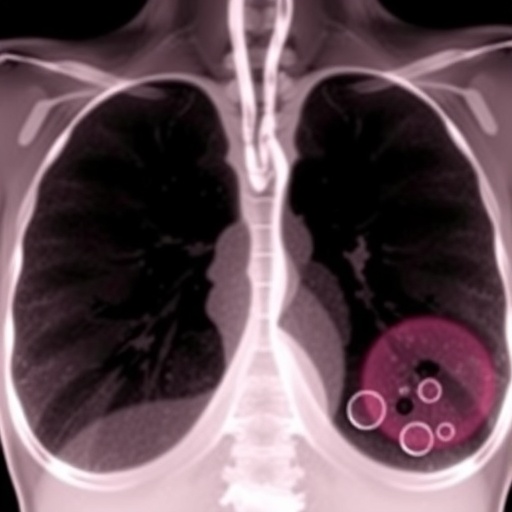

In extensive in vivo experiments employing sophisticated murine models, the investigators evaluated the synergistic effects of localized radiation and CAR T-cell infusion. Radiation was found to induce immunogenic modulation of tumor cells, increasing their susceptibility to CAR T-cell mediated cytotoxicity. This combinatorial approach not only decelerated primary tumor progression but critically inhibited metastatic spread to vital organs such as the lungs and liver—a leading cause of mortality in breast cancer patients.

Moreover, this research addresses a critical unmet need in oncology: the effective targeting of metastatic disease. By demonstrating that targeted radiotherapy can “prime” distant metastatic sites for CAR T-cell mediated eradication, the study provides a framework for overcoming immune resistance and achieving systemic disease control.